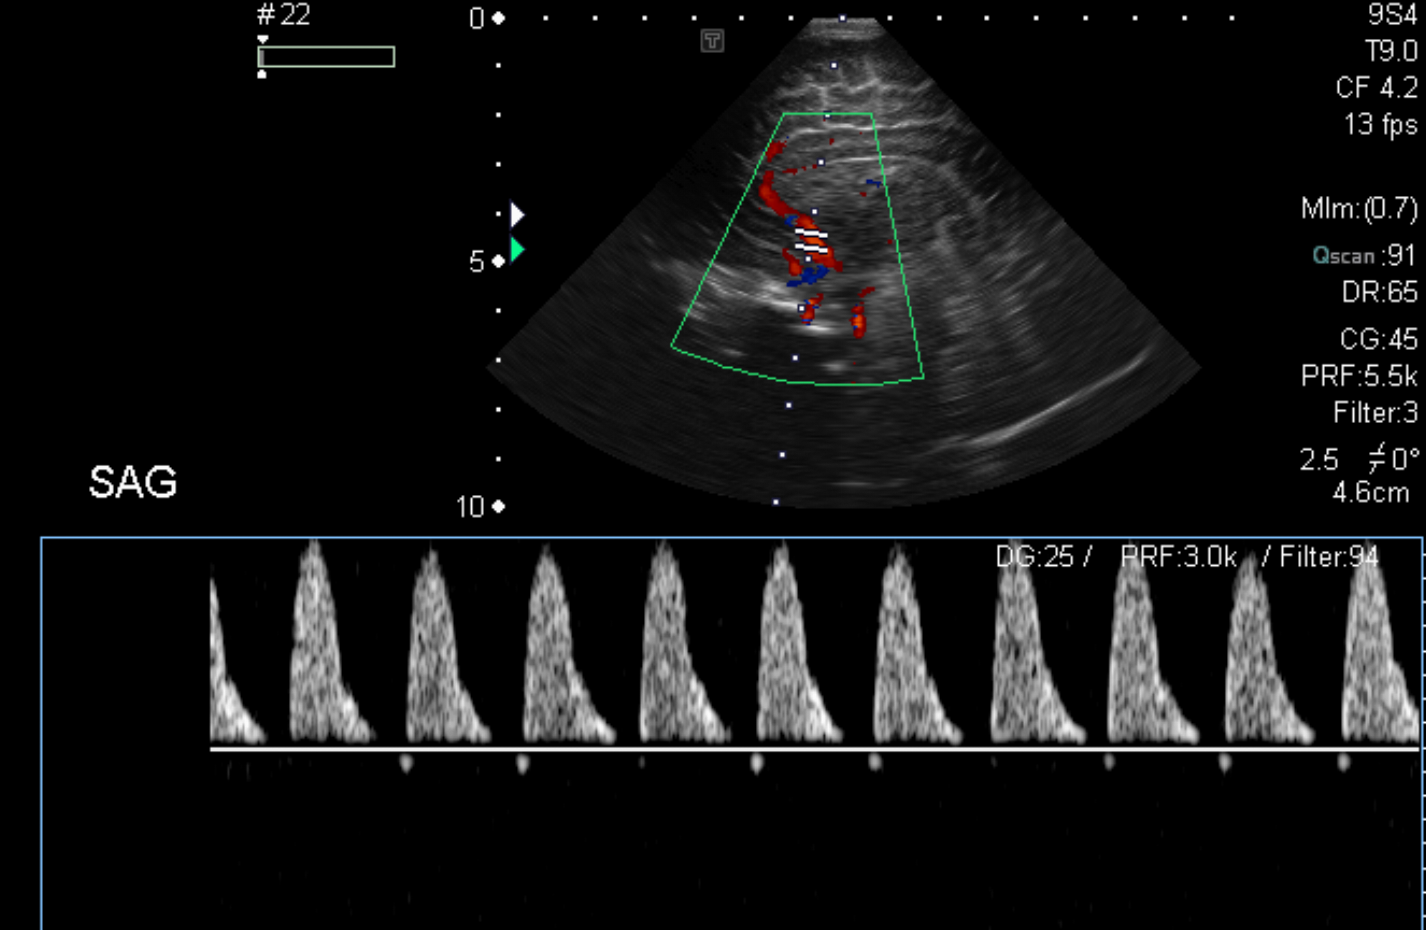

On color Doppler examination, the Resistive index in the anterior cerebral artery is…

There is a loss of the diastolic flow on the Doppler exam. [Yes/No]

There is altered vascularity on Doppler imaging. [Yes/No]